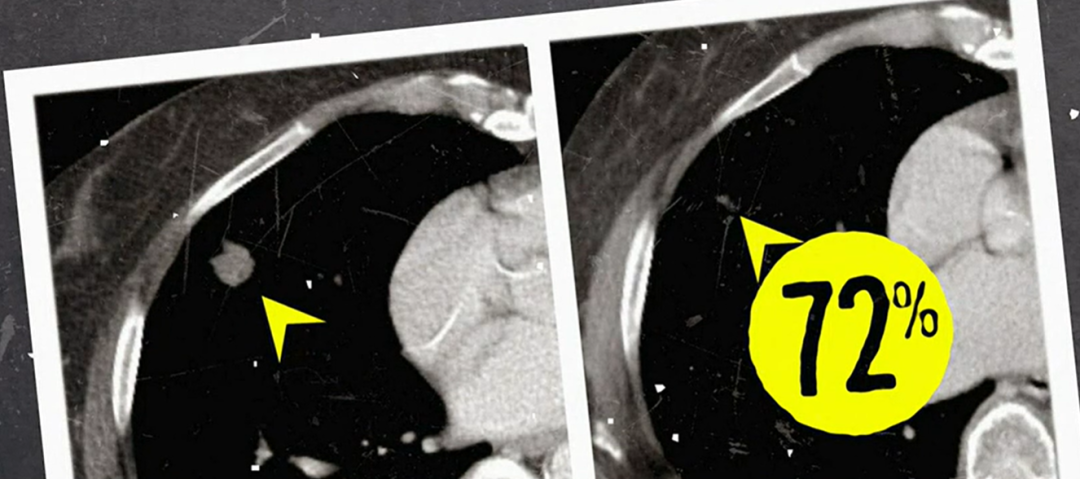

当162亿个免疫细胞回到M女士体内后,奇迹出现了。一个月后,M女士体内的转移灶开始消退;6个月后,经过评估,M女士的病灶竟然消失了72%!